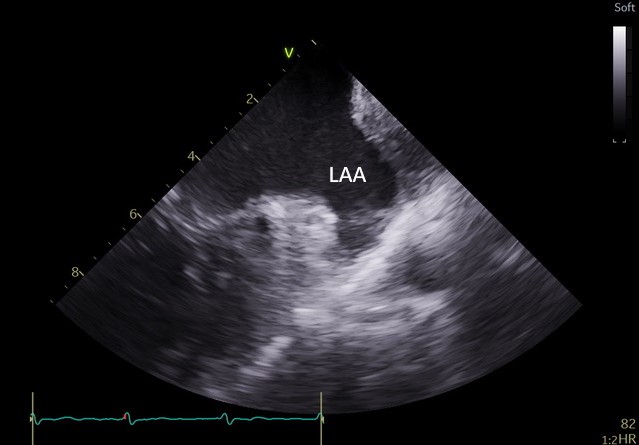

Specjaliści z Pracowni Kardiologii Inwazyjnej I Kliniki Kardiologii UCK przeprowadzili 3 zabiegi zamknięcia uszka lewego przedsionka (ang. LAAO – left atrial appendage occlusion) z wykorzystaniem systemu echokardiografii wewnątrzsercowej (ang. ICE – intracardiac echocardiography).

– U części pacjentów kwalifikowanych do LAAO ryzyko związane z wykorzystaniem obrazowania metodą TEE jest zbyt wysokie ze względu na poważne zmiany chorobowe przełyku. To dotychczas uniemożliwiało wykonanie zabiegu. Obrazowanie metodą ICE pozwala na bezpieczne wykonanie zabiegu zamknięcia uszka lewego przedsionka również w tej grupie chorych, ponieważ specjalną sondę ultrasonograficzną wprowadza się nie do przełyku, lecz przez układ żylny pacjenta, bezpośrednio do jam serca – mówi dr Dariusz Ciećwierz, koordynator Pracowni Kardiologii Inwazyjnej I Kliniki Kardiologii UCK z I Katedry i Kliniki Kardiologii GUMed. – Dodatkową korzyścią tego rozwiązania jest większy komfort pacjenta w trakcie zabiegu, dzięki czemu można uniknąć sedacji czy znieczulenia ogólnego.

– Mogą one powodować ciężkie krwawienia, co sprawia, że u części takich pacjentów nie ma możliwości leczenia przeciwzakrzepowego i proponuje się zabieg LAAO. Z drugiej strony wprowadzenie sondy ultrasonograficznej do zmienionego chorobowo przełyku samo w sobie wiąże się z wysokim ryzykiem wystąpienia krwawienia z żylaków. U takich chorych mamy obecnie możliwość wykonania zabiegu z zastosowaniem obrazowania metodą ICE – tłumaczy prof. Marcin Fijałkowski, koordynator Oddziału Chorób Strukturalnych I Kliniki Kardiologii UCK z I Katedry i Kliniki Kardiologii GUMed.